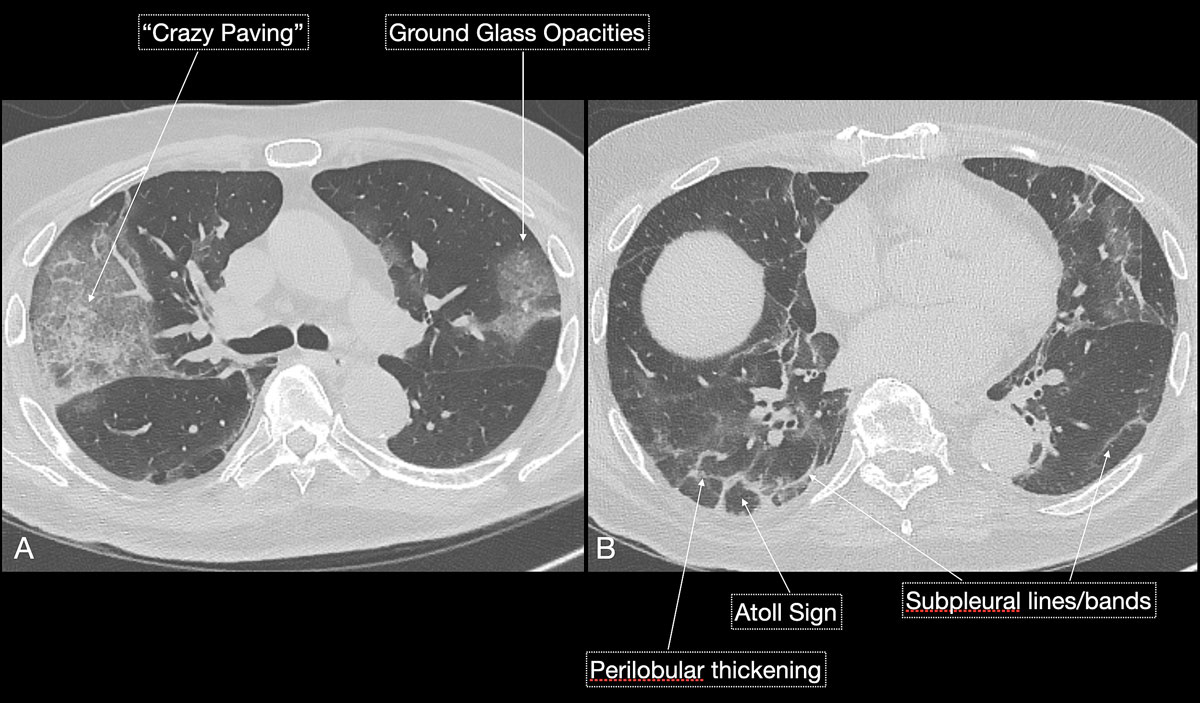

Imaging features in our patient cohort are summarised in table 2 and compared with manifestations observed on CT in Chinese patients [20]. Classic imaging findings are bilateral ground glass opacities with or without areas of consolidation, predominantly with a peripheral or basal lower lobe distribution (figs 3 and 5 ). Unilateral or bilateral ground glass opacities – the hallmark of an early infection (0–4 days) – were observed in almost all COVID-19 patients on chest CT examinations (97% positivity). Given the very subtle appearance of ground glass opacities, their detection on chest x-ray is difficult and often not made prospectively. The second most apparent imaging patterns are consolidations, which are typically multifocal, subpleural/peripheral, or in a peribronchovascular distribution (figs 3 and 5 ). As the disease progresses (5–8 days), the extent of ground glass opacities increases and the amount of consolidation rises (fig. 6). The ground glass opacities progressively transform into consolidative opacities featuring patterns of organising pneumonia of varying extents in the peak stage (10–13 days), before gradually resolving with the patient’s recovery. Typical patterns of organising pneumonia include subpleural lines/bands, perilobular thickening, arcade and atoll signs. Generally, the development of consolidations is a sign of disease progression and is more common in patients above 50 years old and those who have experienced a longer duration of symptoms.

Figure 5 Schematic depiction of typical chest computed tomography (CT) findings for COVID-19: bilateral, focal ground glass opacities or consolidations with peripheral and basal distribution. Ground glass opacities – predominantly seen at earlier stages of infection – are gradually replaced by consolidations during progression of the disease. With progression repair mechanisms with an organising pneumonia pattern become evident, with particular CT signs, such as subpleural lines/bands, perilobular thickening or formation of atoll signs. Another unique pattern seen with disease progression is the “crazy paving” sign, a combination of ground glass opacities and thickened interstitial lines in a mosaic pattern of irregular paving stones.

Reticular opacities are also often seen with COVID-19 patients and likely represent lymphocytic interstitial infiltration, similar to other viral infections (fig. 6). A unique CT pattern with a thickened intra- and interlobular interstitium superimposed on background ground glass opacity was observed in 5–36% of COVID-19 patients. The CT pattern had a specific appearance of “crazy paving”, since it resembles a mosaic of irregular paving stones (figs 6 and 7 ). This sign likely represents the combination of alveolar oedema and interstitial inflammatory changes in the setting of diffuse alveolar damage and is most commonly seen in the progressive stage of the disease [22, 23].

Figure 7 An 84-year-old male patient presented to the emergency department with fever and cough for 4 days after returning from a cruise ship. Intermitted diarrhoea was reported. Nasopharyngeal swabbing was performed, Chest CT was initiated owing to shortness of breath and abnormal Chest x-ray findings (not shown). Findings suggested later stage disease, with typical patterns of “crazy paving” and organising pneumonia. Subpleural lines, perilobular thickening and formation of atoll signs suggested advanced reparative state. The patient recovered from the infection and was discharged home.